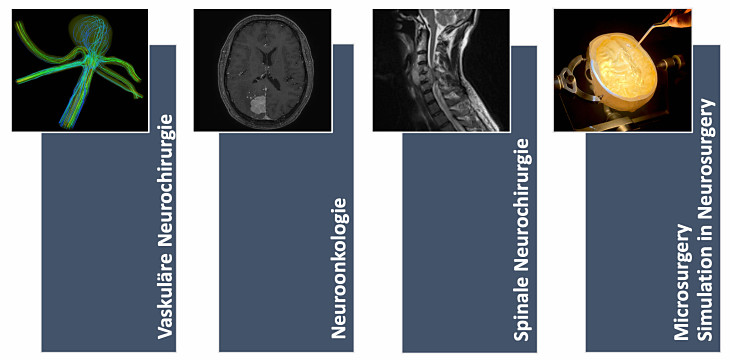

The focus will be on four topics, which will be worked out by the students together with specialists from the various areas of specialization on the basis of current studies and case studies. In the last block in particular, microneurosurgical operation procedures will be introduced to the participants with the aid of patient-specific virtual and mixed reality models.